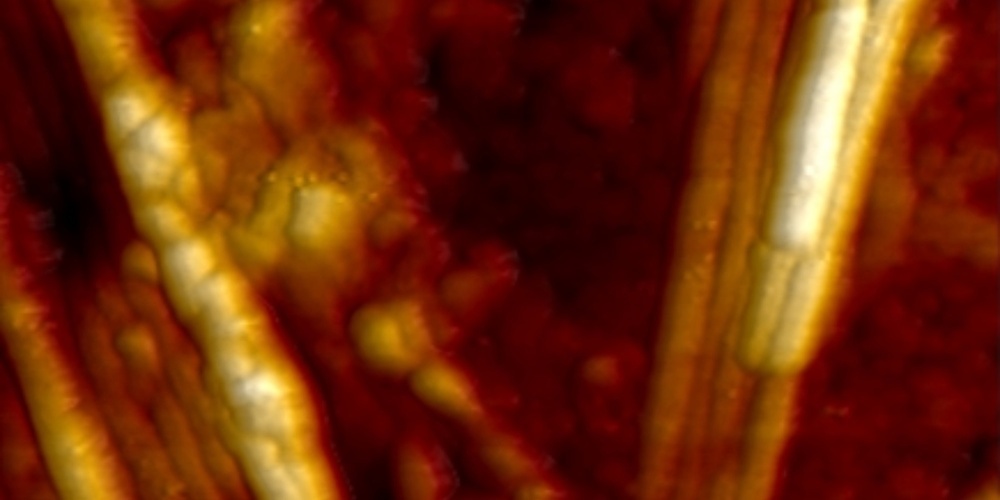

Hochaktive Eiweissstrukturen unter dem Rasterkraftmikroskop: Helle Bereiche zeigen die besonders hohe Aktivität der Nanometer-dünnen Fibrillen an. Bild: Empa

Die besondere Subspezies der Eiweissfibrillen fiel den Forschenden wegen ihrer ungewöhnlichen Eigenschaften auf: Die Kanten und die Oberfläche der sogenannten Superspreader-Fibrillen zeigen eine besonders hohe katalytische Aktivität. An diesen hochaktiven Stellen lagern sich neue Eiweissbausteine an. In der Folge bilden sich von diesen Keimstellen aus neue, langkettige Fibrillen. Die Forschenden gehen davon aus, dass sich diese Fibrillen der zweiten Generation schliesslich ausbreiten und neue Aggregate im Gehirn bilden.

Die Forschenden konnten den Prozess der Fibrillenbildung in Echtzeit verfolgen, und zwar von den ersten Augenblicken bis über die folgenden 250 Stunden. Im Anschluss wurden die Analysen mit molekularen Modellrechnungen abgeglichen und ergänzt. So konnten die Fibrillen aufgrund ihrer Oberflächenstrukturen in Subpopulationen wie beispielsweise «Superspreader» klassifiziert werden. «Damit sind wir einen weiteren Schritt näher daran, zu verstehen, wie sich diese Eiweisse bei Demenzerkrankungen im Gehirn verbreiten», so Empa-Forscher Nirmalraj. Er hofft, dass sich hieraus schliesslich neue Verfahren ableiten lassen, mit denen Demenzerkrankungen besser erkannt und überwacht werden können.

Eine Stunde nach Reaktionsstart sind hochaktive, helle Fibrillen zu erkennen, an denen sich neue Eiweissbausteine ansammeln. Bild: Empa